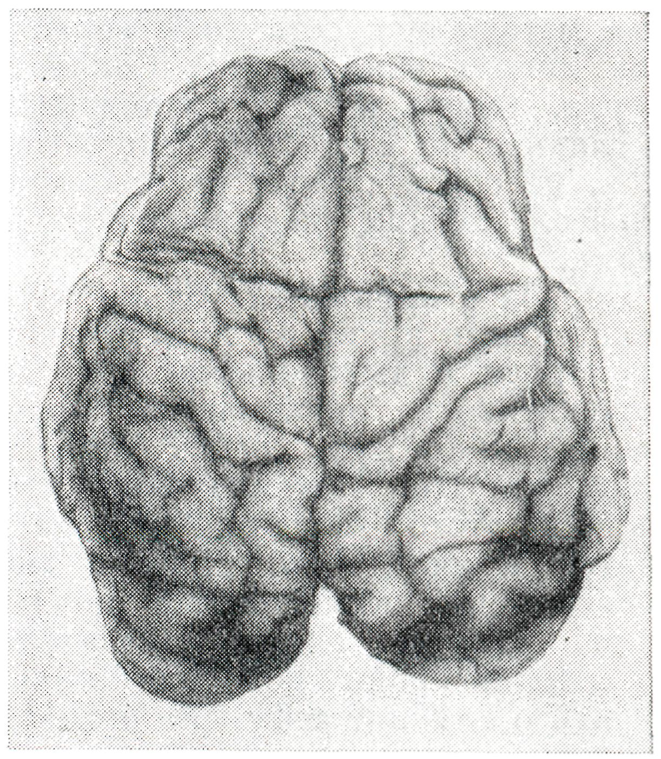

Асфиксия новорожденногоЭтиология и патогенезПричины, приводящие к развитию асфиксии сразу после рождения, многочисленны. Их разделяют на следующие группы: 1) недостаток кислорода и избыток углекислоты или только недостаток кислорода в организме матери (острая кровопотеря, шок, сердечно-сосудистые заболевания, интоксикация, заболевания органов дыхания и системы крови); 2) затруднения циркуляции крови в сосудах пуповины и нарушения маточно-плацентарного кровообращения (патология пуповины и плаценты, токсикозы беременности, перенашивание беременности, аномалии родовой деятельности и др.); 3) заболевания плода и нарушения функции его центральной нервной системы (пороки развития и родовая травма с поражением головного и спинного мозга, тяжелые формы врожденных пороков сердца, гемолитическая болезнь, листериоз, другие инвазии и инфекционные заболевания); 4) полная или частичная непроходимость дыхательных путей при рождении. Патологическая анатомияКожные покровы трупа новорожденного, погибшего от асфиксии, могут быть бледными или синюшными («белая» или «синяя» асфиксия). При осмотре внутренних органов могут наблюдаться обширные геморрагии в ткани различных органов (например, печени) и субкапсулярные гематомы, особенно часто у недоношенных плодов; разрыв такой гематомы может вести к гемоперитонеуму и смерти плода. Спорным остается происхождение обширных кровоизлияний в надпочечники: одни авторы считают их след-ствием асфиксии, другие — прояв¬лением гемолитической болезни но¬ворожденных или родовой травмы. Типичны для асфиксии субарахноидальные (рисунок 5) и внутрижелудочковые кровоизлияния, часто симметричные. Последние регистрируются чаще у недоношенных младенцев. Интрацеребральные микрогеморрагии также располагаются относительно симметрично. При асфиксии, возникшей не сразу после рождения, в легких чаще наблюдается сочетание ателектаза с отеком и гиалиновыми мембранами (смотри Гиалиново-мембранная болезнь новорожденных). Везикулярная эмфизема при асфиксии новорожденных бывает выражена в разной степени и носит либо компенсаторный характер, либо является следствием искусственной вентиляции легких под повышенным давлением (аппаратной или рот в рот); может наблюдаться интерстициальная эмфизема, иногда в сочетании с эмфиземой средостения и пневмотораксом.